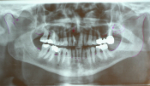

La ATM es la articulación que hace posible abrir y cerrar la boca. La Oclusión es el engranaje producido al contactar las piezas dentarias de la arcada superior con los de la arcada inferior. Cuando dicho engranaje (oclusión) no es perfecto se producen alteraciones en la articulación temporomandibular (ATM) provocando patologías de disfunción articular, que deben ser tratados como cualquier otra afección.

La disfunción cráneo mandibular puede tener dos orígenes que son:

1.    Contactos prematuros de algunas piezas dentales.

2. Alteración de la posición de los cóndilos mandibulares de las ATM y que es debido a desplazamientos de la mandíbula por mala oclusión.